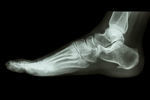

シーバー病/かかとの痛み

【実例】シーバー病

シーバー病の再発

身体に触れると下半身(お尻、太もも、ふくらはぎ、足の甲)の硬さや張りの強い子どもさんが大勢います。

雅樹くんの痛みは右足ですが、両足の硬化が起きています。